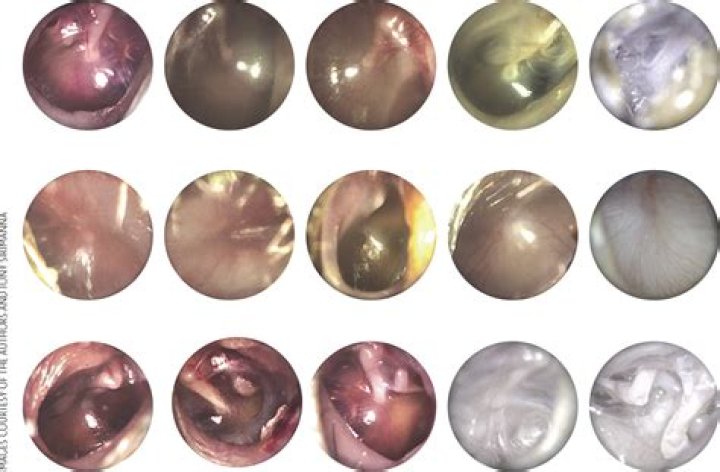

What color is ear infection drainage?

Most commonly, discharge from the ear is ear wax. But it also may include blood or a clear or milky white liquid. The fluid may also be a mix of these. Ear wax is yellow to orange-brown in color and is generally not a medical problem.